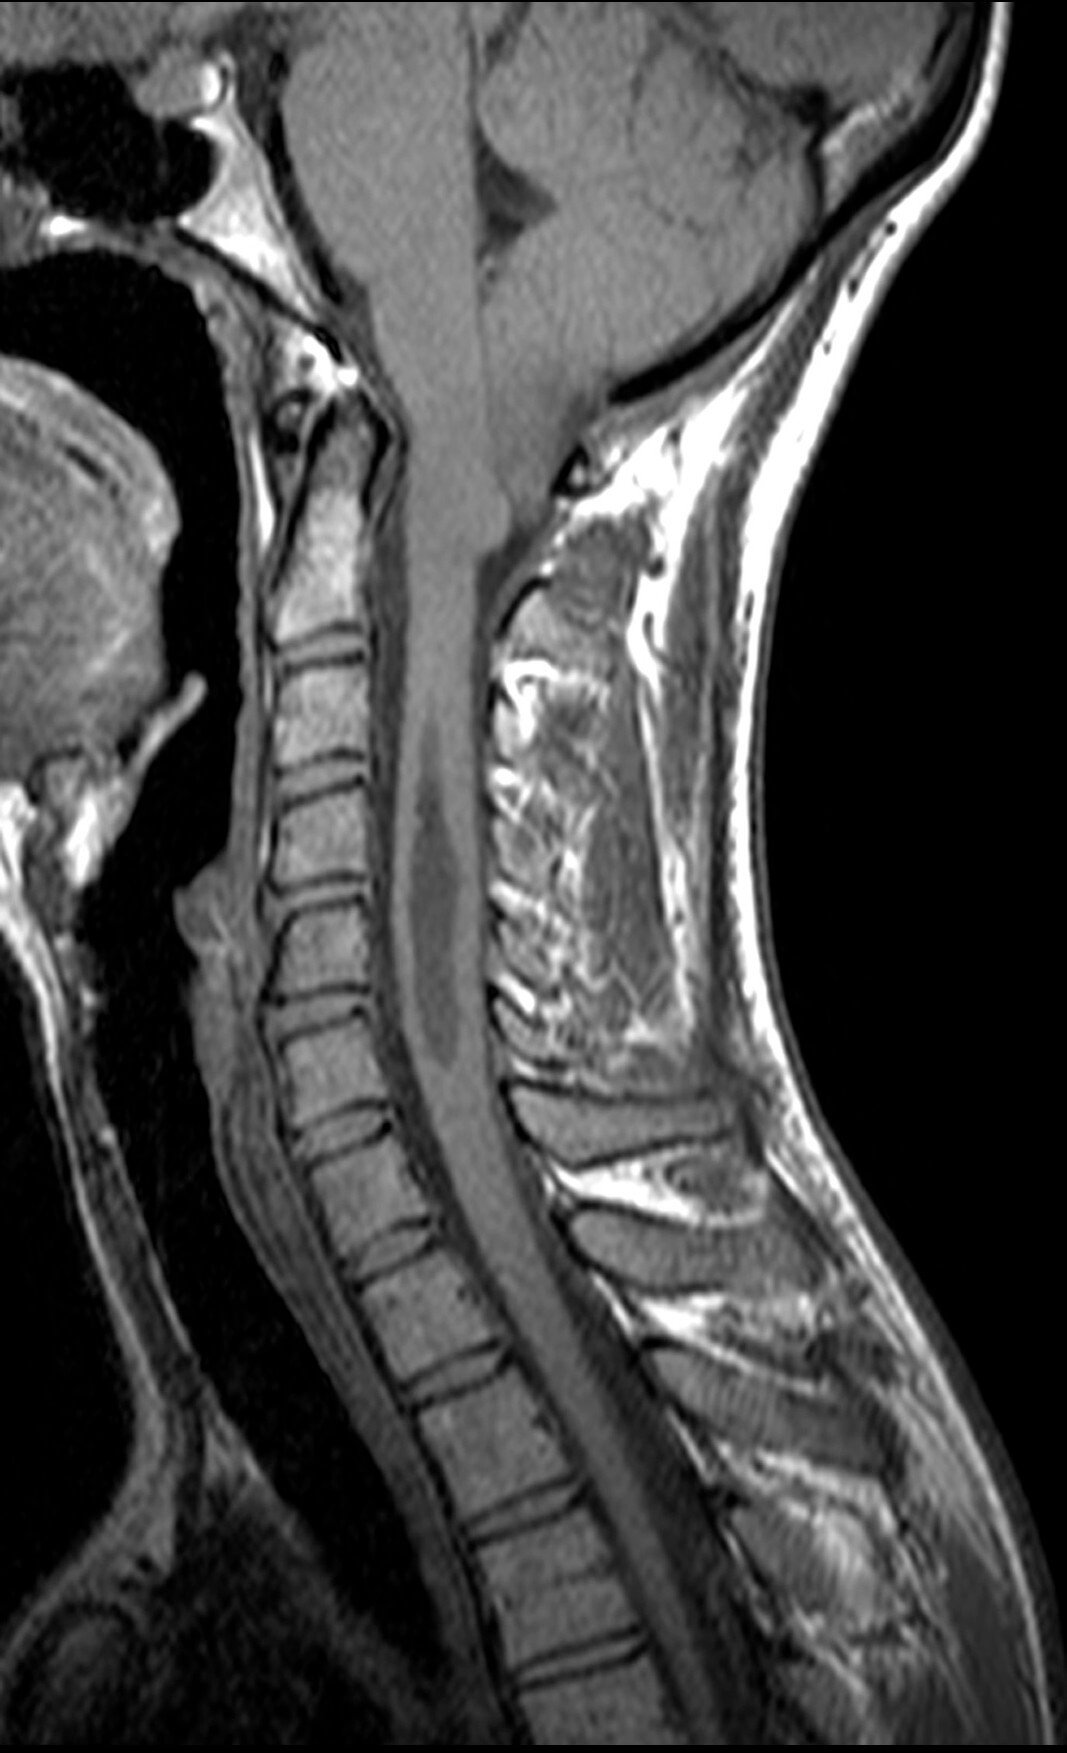

Spine